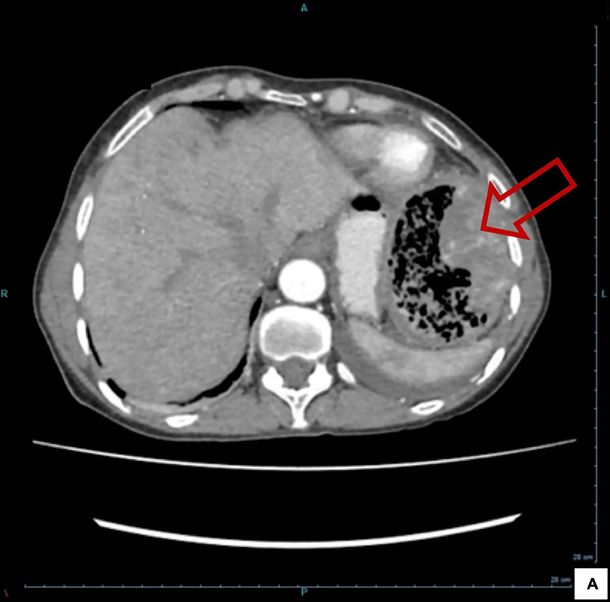

Alarmada por la aparición repentina de los síntomas, la paciente acudió al hospital, donde las ecografías revelaron una gran gasa en el abdomen. Los médicos creían que el polizón pegajoso se había quedado en su colon durante la operación dos décadas antes.